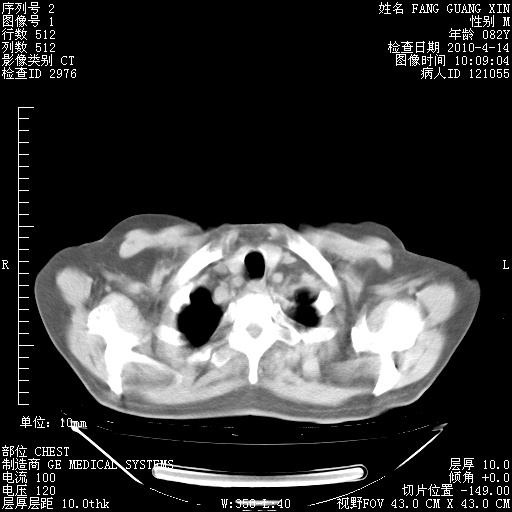

4月28日肺部CT——再次出现类似去年5月9日——透光度降低,(影像科认为)“间质性”改变。

4月28日肺部CT——再次出现类似去年5月9日——透光度降低,“间质性”改变。